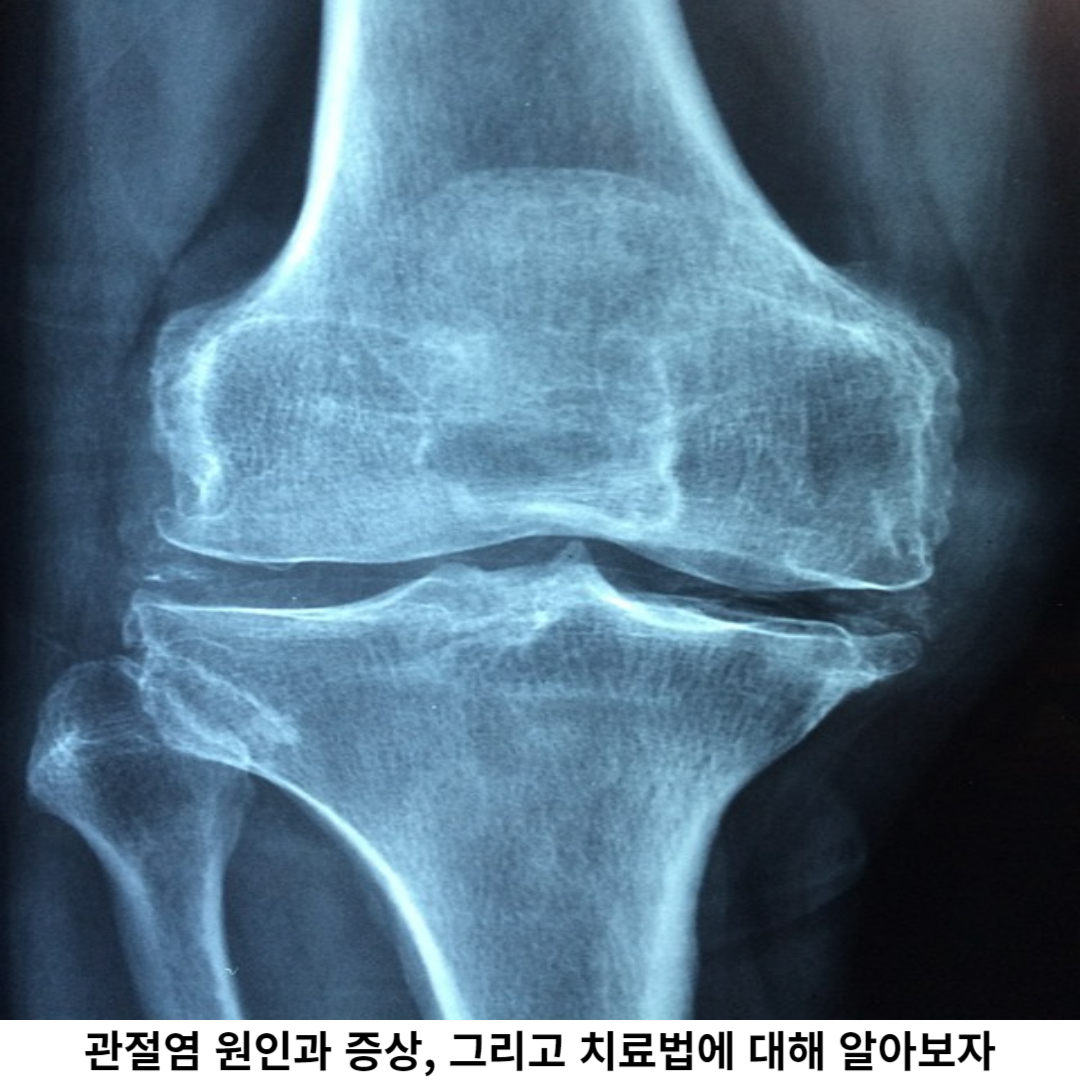

관절염은 인체의 관절 부위에서 발생하는 만성적인 염증 질환으로, 주로 관절 주변의 연골과 뼈조직에 영향을 미칩니다. 이 염증은 일상생활이나 관절을 움직일 때 통증, 기능 저하 등 여러 가지 증상으로 발생될 수 있습니다.

관절염은 여러 가지 원인에 의해 발생할 수 있으며, 연령, 유전적인 요인, 관절 손상, 면역 질환 등이 원인은 여려가지입니다. 관절염은 치료하지 않으면 진행이 지속되어 관절 손상이 발생됩니다. 관절염은 조기 진단과 치료가 매우 중요합니다.